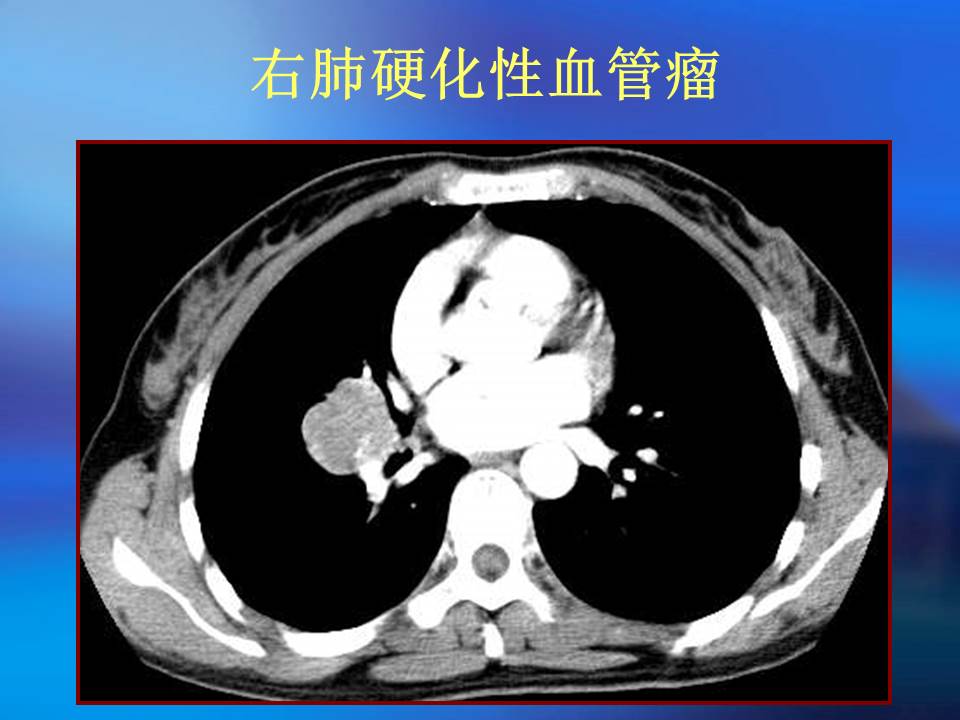

肺良性肿瘤